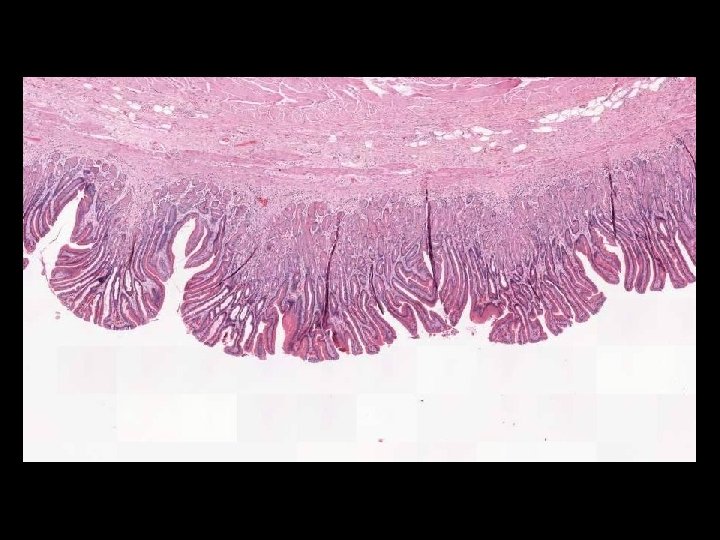

IMAGES